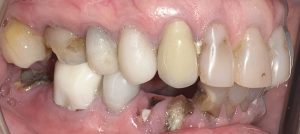

Patient with missing teeth and full mouth of infection & decay seeking help of a biological dentist

The patient presented to Virginia Biological Dentistry for a comprehensive biological evaluation after experiencing extensive dental breakdown and ongoing infection. Examination revealed advanced decay in the upper dentition, missing teeth, and widespread infection affecting all remaining lower teeth, rendering the lower teeth non-salvageable.

Cavities and Infections and broken teeth